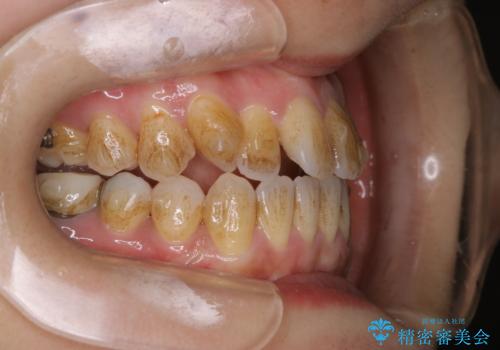

- インビザライン矯正治療中に頑固に付着した着色を取りたいとのことでした。PMTC60分コースを行いました。

マウスピース矯正インビザライン治療では、歯の表面にアタッチメントという突起を設定します。(アタッチメントは歯の動きを効率的に移動するためのものです)

アタッチメントが歯に付くと、表面が凸凹し磨き残しが多くなったりと、プラークや歯石・着色がつきやすくなることがあります。